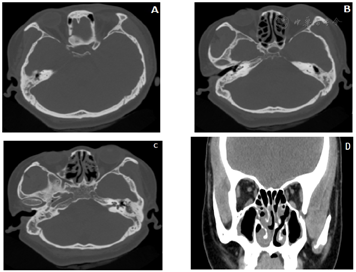

(1)鼻窦CT检查:双侧额窦未见发育,双侧蝶窦窦腔较小,双侧上颌窦、筛窦及蝶窦黏膜增厚,窦壁骨质未见异常改变;双侧鼻腔黏膜增厚,右侧中、下鼻甲肥厚,鼻中隔轻度向左偏曲。双侧乳突气化不良,双侧中耳鼓室及乳突窦见黏膜增厚影及积液影(图1)。

胸部扫描还可以看到明确存在全内脏反位:主要表现为患者右位心、纵隔内血管转位、腹部脏器肝脾胃镜面转位。鼻窦或头颅CT可以明确诊断副鼻窦炎及了解窦鼻骨质结构。可观察鼻窦黏膜增厚及密度增高影,鼻腔内息肉、鼻窦窦壁骨质增生或邻近骨质变薄等征象。部分患者可看到中耳炎表现。